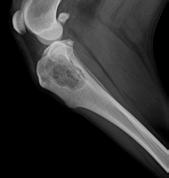

La Fondazione Salute Animale si propone di tutelare la salute ed il benessere degli animali a stretto contatto con l’uomo, gestisce una Centrale di Lettura Ufficiale per la Displasia dell’Anca e del Gomito del Cane, riconosciuta dall’ENCI, ed organizza il controllo diagnostico di altre malattie genetiche (oculopatie, cardiopatie, neuropatie, nefropatie, coagulopatie e lussazione della rotula) in collaborazione con le Società Scientifiche Specialistiche.

CORSO DI BASE PER IL CONTROLLO DELLA DISPLASIA DELL’ANCA E DEL GOMITO, DELLA LUSSAZIONE DELLA ROTULA E DI ALTRE PATOLOGIE SCHELETRICHE EREDITARE DEL CANE 16-17-18 Giugno 2023 - Direttore del corso Dott. Aldo Vezzoni

CORSO DI AGGIORNAMENTO PER IL CONTROLLO DELLA LUSSAZIONE DELLA ROTULA NEL CANE DI RAZZA E SUL CONTROLLO HD/ED 17 Giugno 2023 - Direttore del corso Dott. Aldo Vezzoni